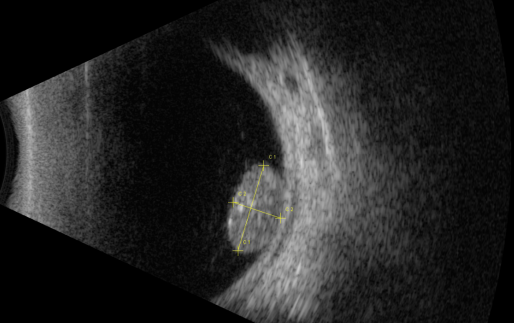

視網(wǎng)膜母細(xì)胞瘤的分類和治療

視網(wǎng)膜母細(xì)胞瘤是嬰幼兒常見的眼內(nèi)惡性腫瘤,可危害患者的視力、眼球和生命。其惡性程度高,多發(fā)于兒童,尤其是3歲以下的兒童,常表現(xiàn)為白瞳癥,可侵及單眼或雙眼。

根據(jù)腫瘤的表現(xiàn)和發(fā)展過程可分為眼內(nèi)期、青光眼期、眼外期和全身轉(zhuǎn)移期。

開始在眼內(nèi)生長時外眼正常,因患兒年齡小,不能自述有無視力障礙,因此本病早期一般不易被家長發(fā)現(xiàn)。當(dāng)腫瘤增殖突入玻璃體或接近晶體時,瞳孔區(qū)出現(xiàn)黃白色反光,如貓眼樣(“黑貓眼”),此時常因視力障礙而瞳孔散大、白瞳癥或斜視被家長發(fā)現(xiàn)。